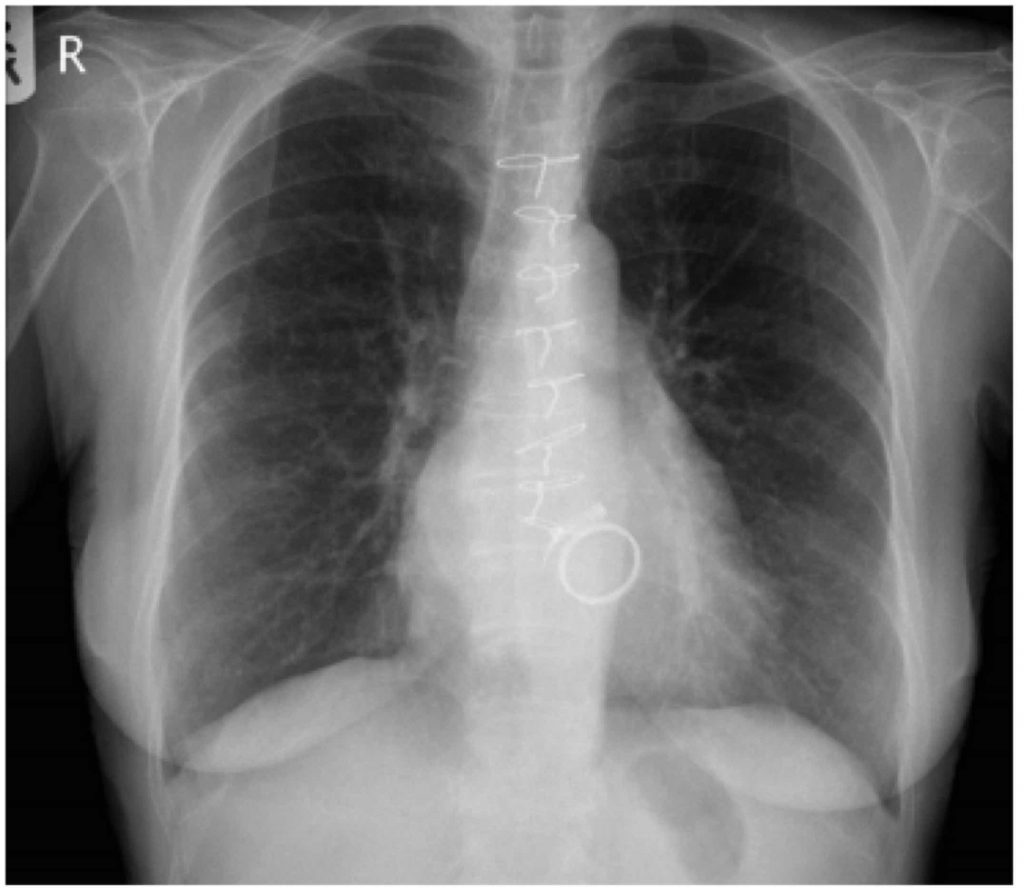

Along with the diaphragm, the clinician should also be making note of the costophrenic angles. They should be sharp bilaterally and are formed from the dome of each hemidiaphragm and lateral chest wall. The loss of a costophrenic angle (blunting) also often indicates the presence of fluid or consolidation. There can also be flattening of the diaphragms with costophrenic blunting. This alone with hyperinflation (think back to R.I.P) is an indicator of emphysematous changes (COPD). In the two images above note the hyperinflation, blunting of the costophrenic angles and especially the flattened diaphragms. This is a very ‘classic’ example of COPD:

Example 1

Rotation – no

Inspiration – mildly hyperinflated but not grossly

Penetration – appropriate

Prior – No

Airway – Trachea, carina and right/left bronchi all medial and also patent

Breathing – Right lower lobe opacification, airway markings bilaterally to chest wall

Cardiac – not enlarged, right and left cardiac borders not obscured

Diaphragm – sharp bilateral costophrenic angles, right diaphragm a bit obscured by air

bronchograms. Some increased lucency under left diaphragm correlating with gastric bubble

Everything else – Aortic knuckle and window also appropriate, no fractures, bilateral breast tissue symmetrical, no heart valves or lines noted

Diagnosis: RLL consolidation. Without history this would likely be diagnosed as a RLL Pneumonia